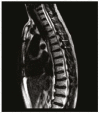

The focal calcification or ossification of the ligamentum flavum is a rare cause of thoracic myelopathy and most often occurs among individuals of Japanese descent. It is rare in other ethnic groups and in individuals below the age of 50. It is most often described at the lower thoracic level, being uncommon in the lumbar region and rare in the cervical region. Here, we present the case of a 44-year-old White female patient who sought medical attention with an eight-month history of paraesthesia of the lower limbs and progressive difficulty in walking. The clinical profile, together with computed tomography and nuclear magnetic resonance imaging of the spine, led to a diagnosis of compressive thoracic myelopathy due to ossification of the ligamentum flavum in the thoracic and lumbar spine. The patient underwent laminectomy and dissection of some of the affected ligamentum flavum, without any intraoperative complications. After three months of clinical follow-up, the patient had progressed favorably, having no sensory complaints and again becoming ambulatory.